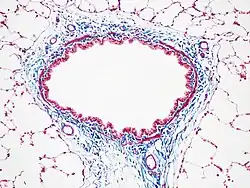

Masson's trichrome stain

Masson's trichrome is a three-colour staining procedure used in histology. The recipes emerged from Claude L. Pierre Masson's (1880–1959) original formulation have different specific applications, but all are suited for distinguishing cells from surrounding connective tissue.

Most recipes produce red keratin and muscle fibers, blue or green collagen and bone, light red or pink cytoplasm, and dark brown to black cell nuclei.

Standard applications: Masson's trichrome staining is widely used to study muscular pathologies (muscular dystrophy), cardiac pathologies (infarct), hepatic pathologies (cirrhosis) or kidney pathologies (glomerular fibrosis). It can also be used to detect and analyze tumors on hepatic and kidney biopsies.[1]

Another common variant is the Masson trichrome & Verhoeff stain, which combines the Masson trichrome stain and Verhoeff's stain.[2] This combination is useful for the examination of blood vessels; the Verhoeff stain highlights elastin (black) and allows one to easily differentiate small arteries (which typically have at least two elastic laminae) and veins (which have one elastic lamina).